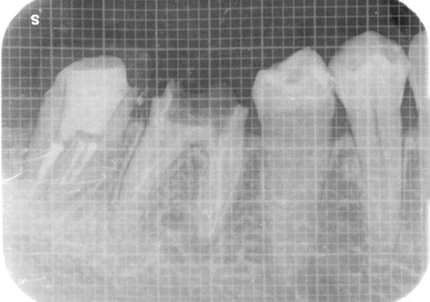

18.インプラント埋入後 パノラマレントゲン